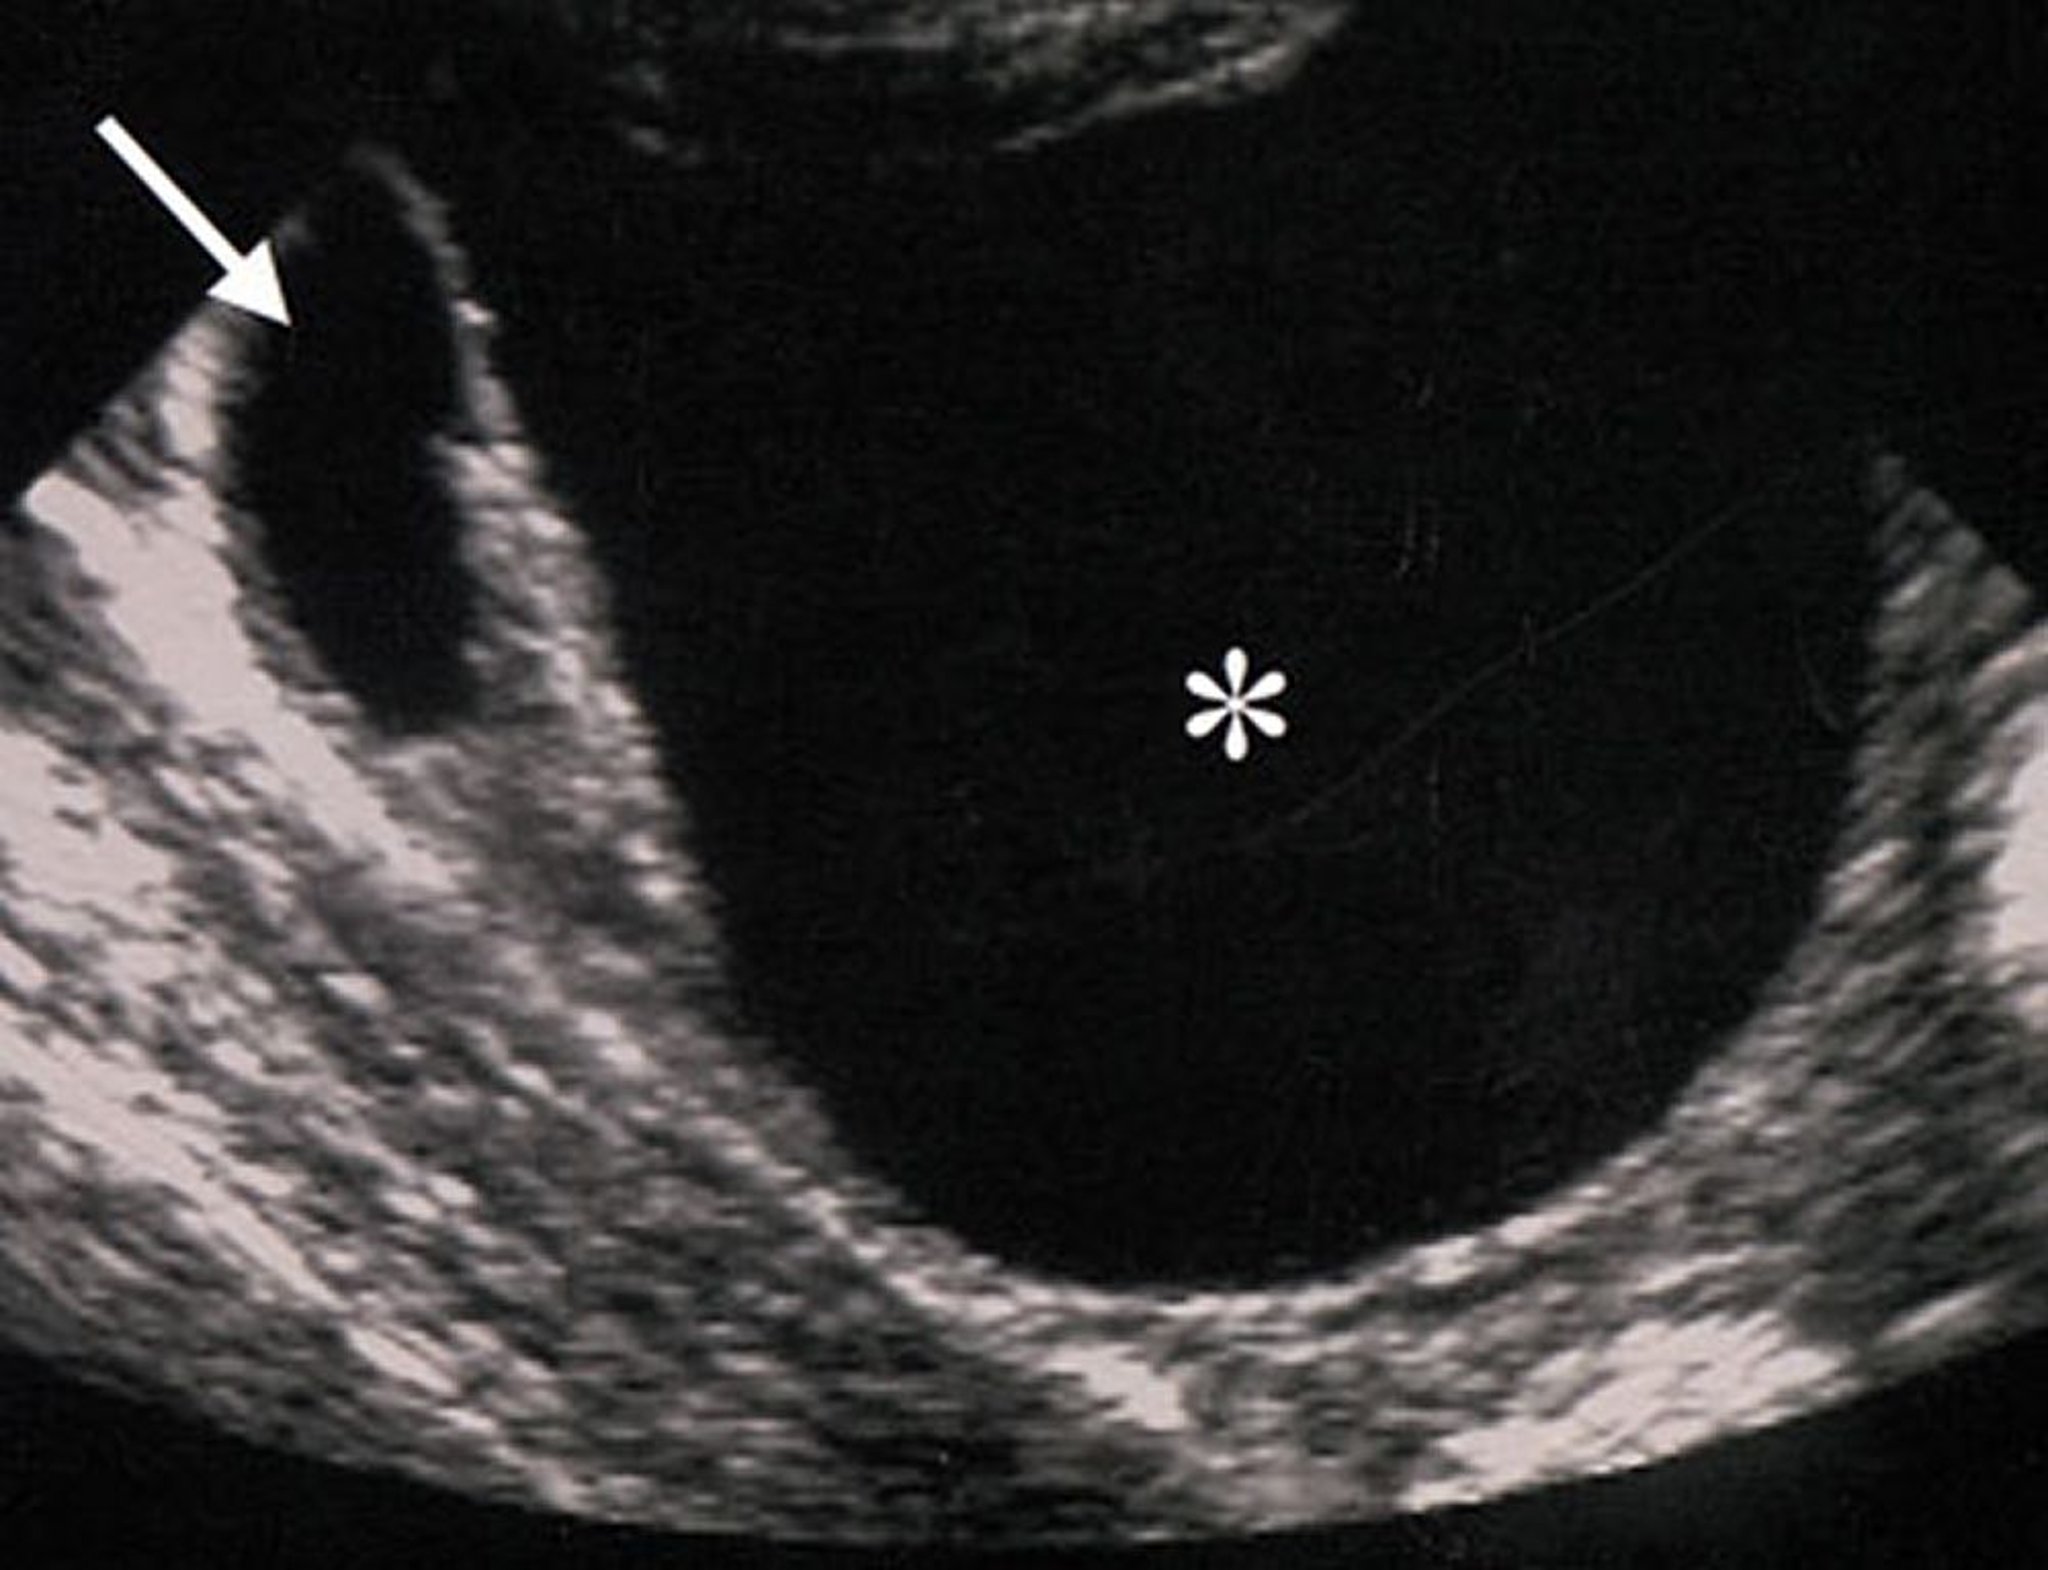

Ultrasound of a Benign Ovarian Mass

Ultrasound characteristics of this ovarian mass (indicated by an asterisk) suggest that the mass is benign. The mass is anechoic (suggesting absence of solid components), regular, well-circumscribed, and without wall thickening or excrescences.